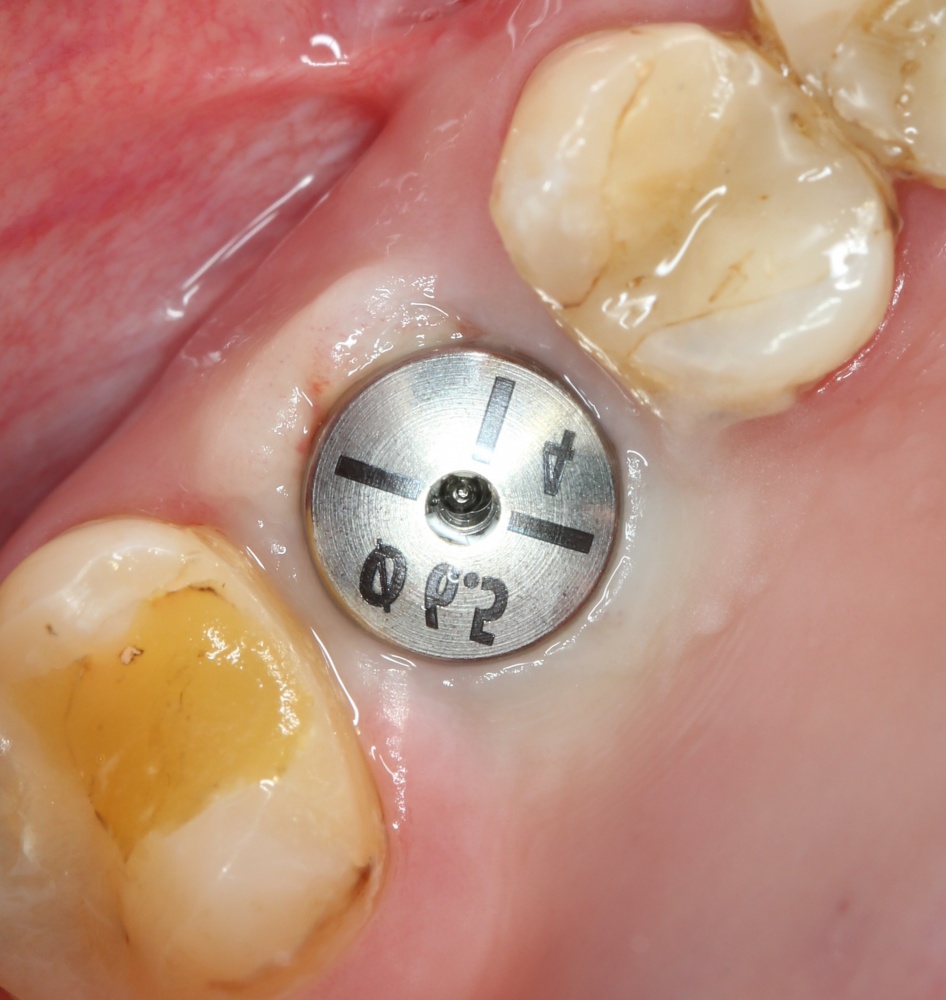

Мы встретились как старые друзья. Честно признаюсь, я очень переживал. Я ожидал увидеть какую-нибудь жуть, утраченную кость, периимплантит, разрушенный вхлам протез и всё такое. Но… всё оказалось не так плохо:

Но фиг с ними, с протезами. Это временные композитные коронки, их не так уж сложно заменить. Меня волнует другой вопрос:

— что там с имплантатами и костной тканью?

Для этого мы сделали КЛКТ:

И КЛКТ показала нам, что с имплантатами и окружающей костью всё зашибись. Через 12 лет после операции, отсутствия наблюдения, пофигизма в замене временных коронок! Нужны ли тебе еще какие-нибудь доводы в пользу долгосрочной эффективности метода?

А дальше всё просто. Я попросил своего коллегу Ивана Алгазина заменить износившиеся временные коронки на постоянные керамические — но с учётом современных реалий и требований:

Серия контрольных снимков на этапах:

Вот так закончилась 12-летняя эпопея Зинаиды с восстановлением зубов на нижней челюсти. Через пару дней она уехала на экскурсию в Санкт-Петербург (на всякий случай, мы попросили задержаться в России, вдруг потребуется коррекция), а оттуда — домой, в дружественную страну. Судя по тому, что она нам пишет — у неё всё прекрасно и хорошо. Зинаида обещает не пропускать профилактические осмотры и наблюдаться у стоматолога по месту жительства.